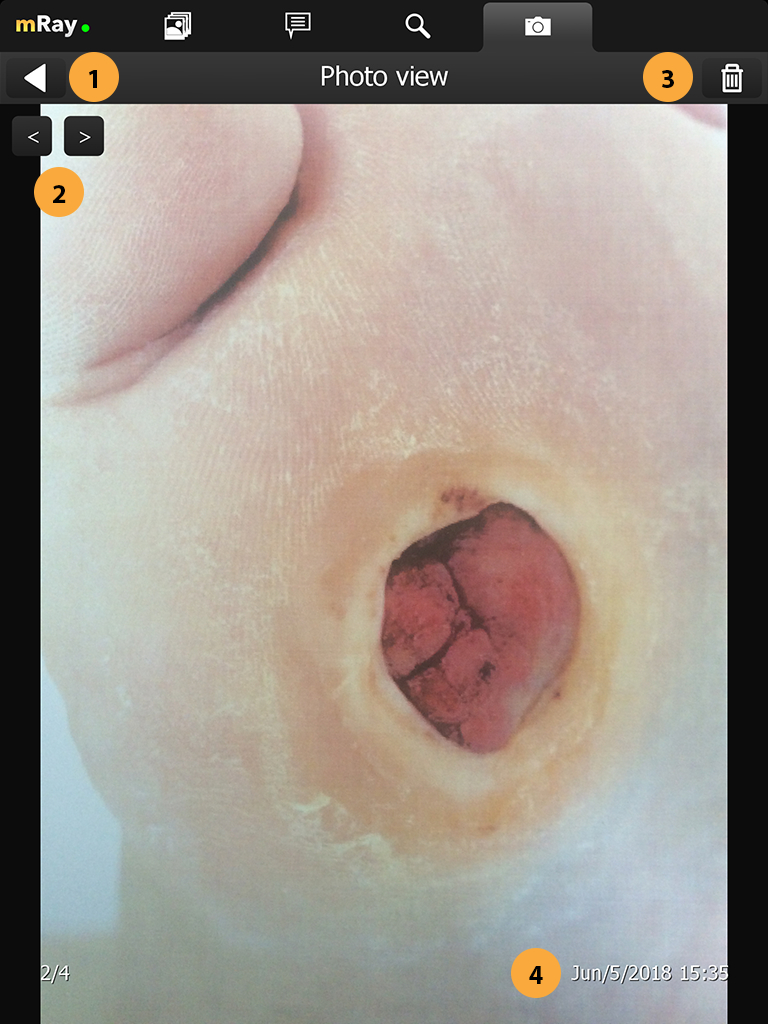

15.3. Body part

In the next step you are asked to to select a body part to which the selected photogroup belongs to. The selected body part defaults to "Unspecified" and is displayed in a label (Point 4). To select a body part just press on the human. To switch between front and back view you can press the corresponding button (Point 2). For navigation purposes you it’s displayed which side is left or right (Point 3).

-

Body part selection. Click on a body part to select it.

-

Rotates the body part selection so you can select parts on the front and back of the patient.

-

Shows the correct direction relative to the body part selection.

-

Shows the name of the currently selected body part.

-

Confirm the selection and proceed to the next step.

By tapping on the next button you will continue to the orderview.